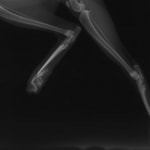

症例3:キルシュナーワイヤーのピンニングによる整復

ペルシャ猫 11ヶ月齢 雄

他院にて左大腿骨遠位の成長板骨折(salter-harrisⅠ型)が認められており、治療相談を目的として来院。当院にて、キルシュナーワイヤーを用いたピンニングにより骨折部位の整復を行いました。術後の経過は良好で、現在も経過観察中です。

術前レントゲン

術後レントゲン